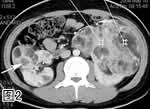

图2. 增强CT扫描和图3. 增强CT冠状位多层面重组像,示双肾巨大肿物,密度不均,可见多发脂肪密度灶(箭号)。肝内亦见一脂肪密度灶(箭头)。